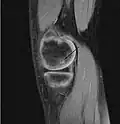

| A large flap lesion in the femur head typical of late stage Osteochondritis dissecans. In this case, the lesion was caused by avascular necrosis of the bone just under the cartilage. | |

Magnetic resonance imaging (MRI) is useful for staging OCD lesions, evaluating the integrity of the joint surface, and distinguishing normal variants of bone formation from OCD by showing bone and cartilage edema in the area of the irregularity. MRI provides information regarding features of the articular cartilage and bone under the cartilage, including edema, fractures, fluid interfaces, articular surface integrity, and fragment displacement.[37][38] A low T1 and high T2 signal at the fragment interface is seen in active lesions. This indicates an unstable lesion or recent microfractures.[30] While MRI and arthroscopy have a close correlation, X-ray films tend to be less inductive of similar MRI results.[38]